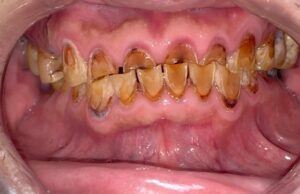

すごくわかりやすく言うと、外力などで歯がすり減ったり、削れていったりする状態です。年齢とともに、多くの人が多少の変形は起こすのですが、かなり病的に削れてしまっている方もいます。また、1、2本だけ削れている方もいれば数本単位、さらには残っているは全部が削れてしまっている方もいます。図1は上顎左から3本目の犬歯(糸切り歯)の先端が直線になっているのがわかると思います。図2は長年にわたる咬耗が極度に進行し、見えているは全ての歯が極度に削れており、上の前歯などは原形をとどめていません。もちろんここまでくると正常ではありませんが、むし歯ではありません。 咬耗は長年にわたる歯ぎしり、くいしばりが主な原因です。多くの場合は痛みなどの症状はありません。ご本人の希望などで形態修正をすることもありますが、多くの場合で困難です。人間の体で最も硬い組織の歯の表面が削れるだけの力が加わりますから、それに抵抗するものを作らなければならないからです。

図2 長年の歯ぎしり、食いしばりによって多くの歯が極度に削れている